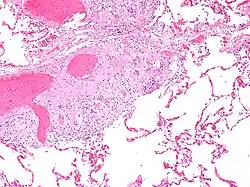

Sarkoidoza, choroba Besniera-Boecka-Schaumanna (łac. sarcoidosis) – choroba układu odpornościowego charakteryzująca się powstawaniem ziarniniaków (małych grudek zapalnych), które nie podlegają martwicy. Praktycznie każdy organ może być nią dotknięty, chociaż najczęściej pojawia się w węzłach chłonnych i płucach. Objawy mogą się pojawić nagle, ale najczęściej postępują stopniowo. W obrazie rentgenowskim płuc sarkoidoza może przypominać gruźlicę lub chłoniaka.

Sarkoidoza jest chorobą układową i dlatego może dotknąć każdy narząd. Mało specyficzne są najczęstsze objawy choroby, takie jak: zmęczenie, na które nie ma wpływu sen, bóle o różnym natężeniu, suchość oczu, zamazane widzenie, skrócenie oddechu, suchy, ostry kaszel, uszkodzenia skóry.